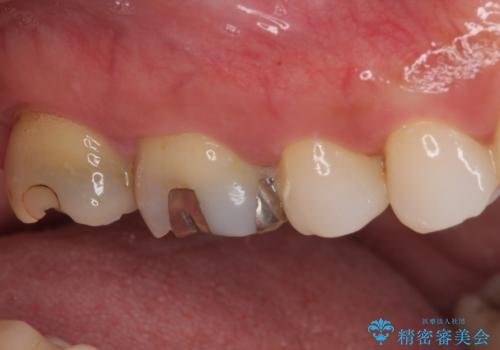

- むし歯治療途中で放置していた奥歯から、歯磨きの度に出血するとのことで来院された患者様です。

隣接する部分の間のむし歯が歯肉の奥深くにまで及んでおり、歯肉が腫れやすい状態となっていたため、歯肉の切除並びに歯槽骨の形態修正を行い、虫歯が歯肉の外に出てくるようにした上で、オールセラミックにて補綴することとしました。